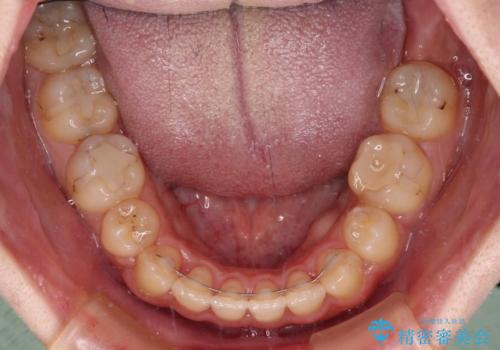

- 八重歯と上下前歯のでこぼこを気にして来院された患者様です。

上下前歯部叢生のスペース獲得のため、上下顎左右小臼歯各1歯(計4本)と全ての親知らずを抜歯して、矯正治療を行うこととしました。